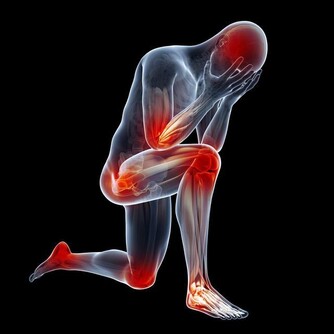

胯骨疼痛是許多人會遇到的疼痛症狀,它可能來自於骶髂關節、腰椎等多個部位的病變。當感到胯部或髂骨處隱隱作痛時,我們該如何判斷其成因?原因明確了,治療才能更有針對性。

胯骨疼痛是較常見的症狀,臨床上將其定義為髖關節周圍軟組織出現的疼痛感。胯骨區域包含肌肉、韌帶、神經、血管等多個解剖結構,任何一個部位發生病變都可能導致疼痛。

胯骨疼痛的確切部位各有不同,可能位於髖關節的內側、外側、前側或後側。臨床研究顯示,內側和前側疼痛較多。

這主要是因為髖關節內側有多個韌帶附著點,承受較大的應力,而前側則有髕腱肌肉附著,也處於重要的負重位置。這兩個部位微小損傷就會引起胯骨疼痛。